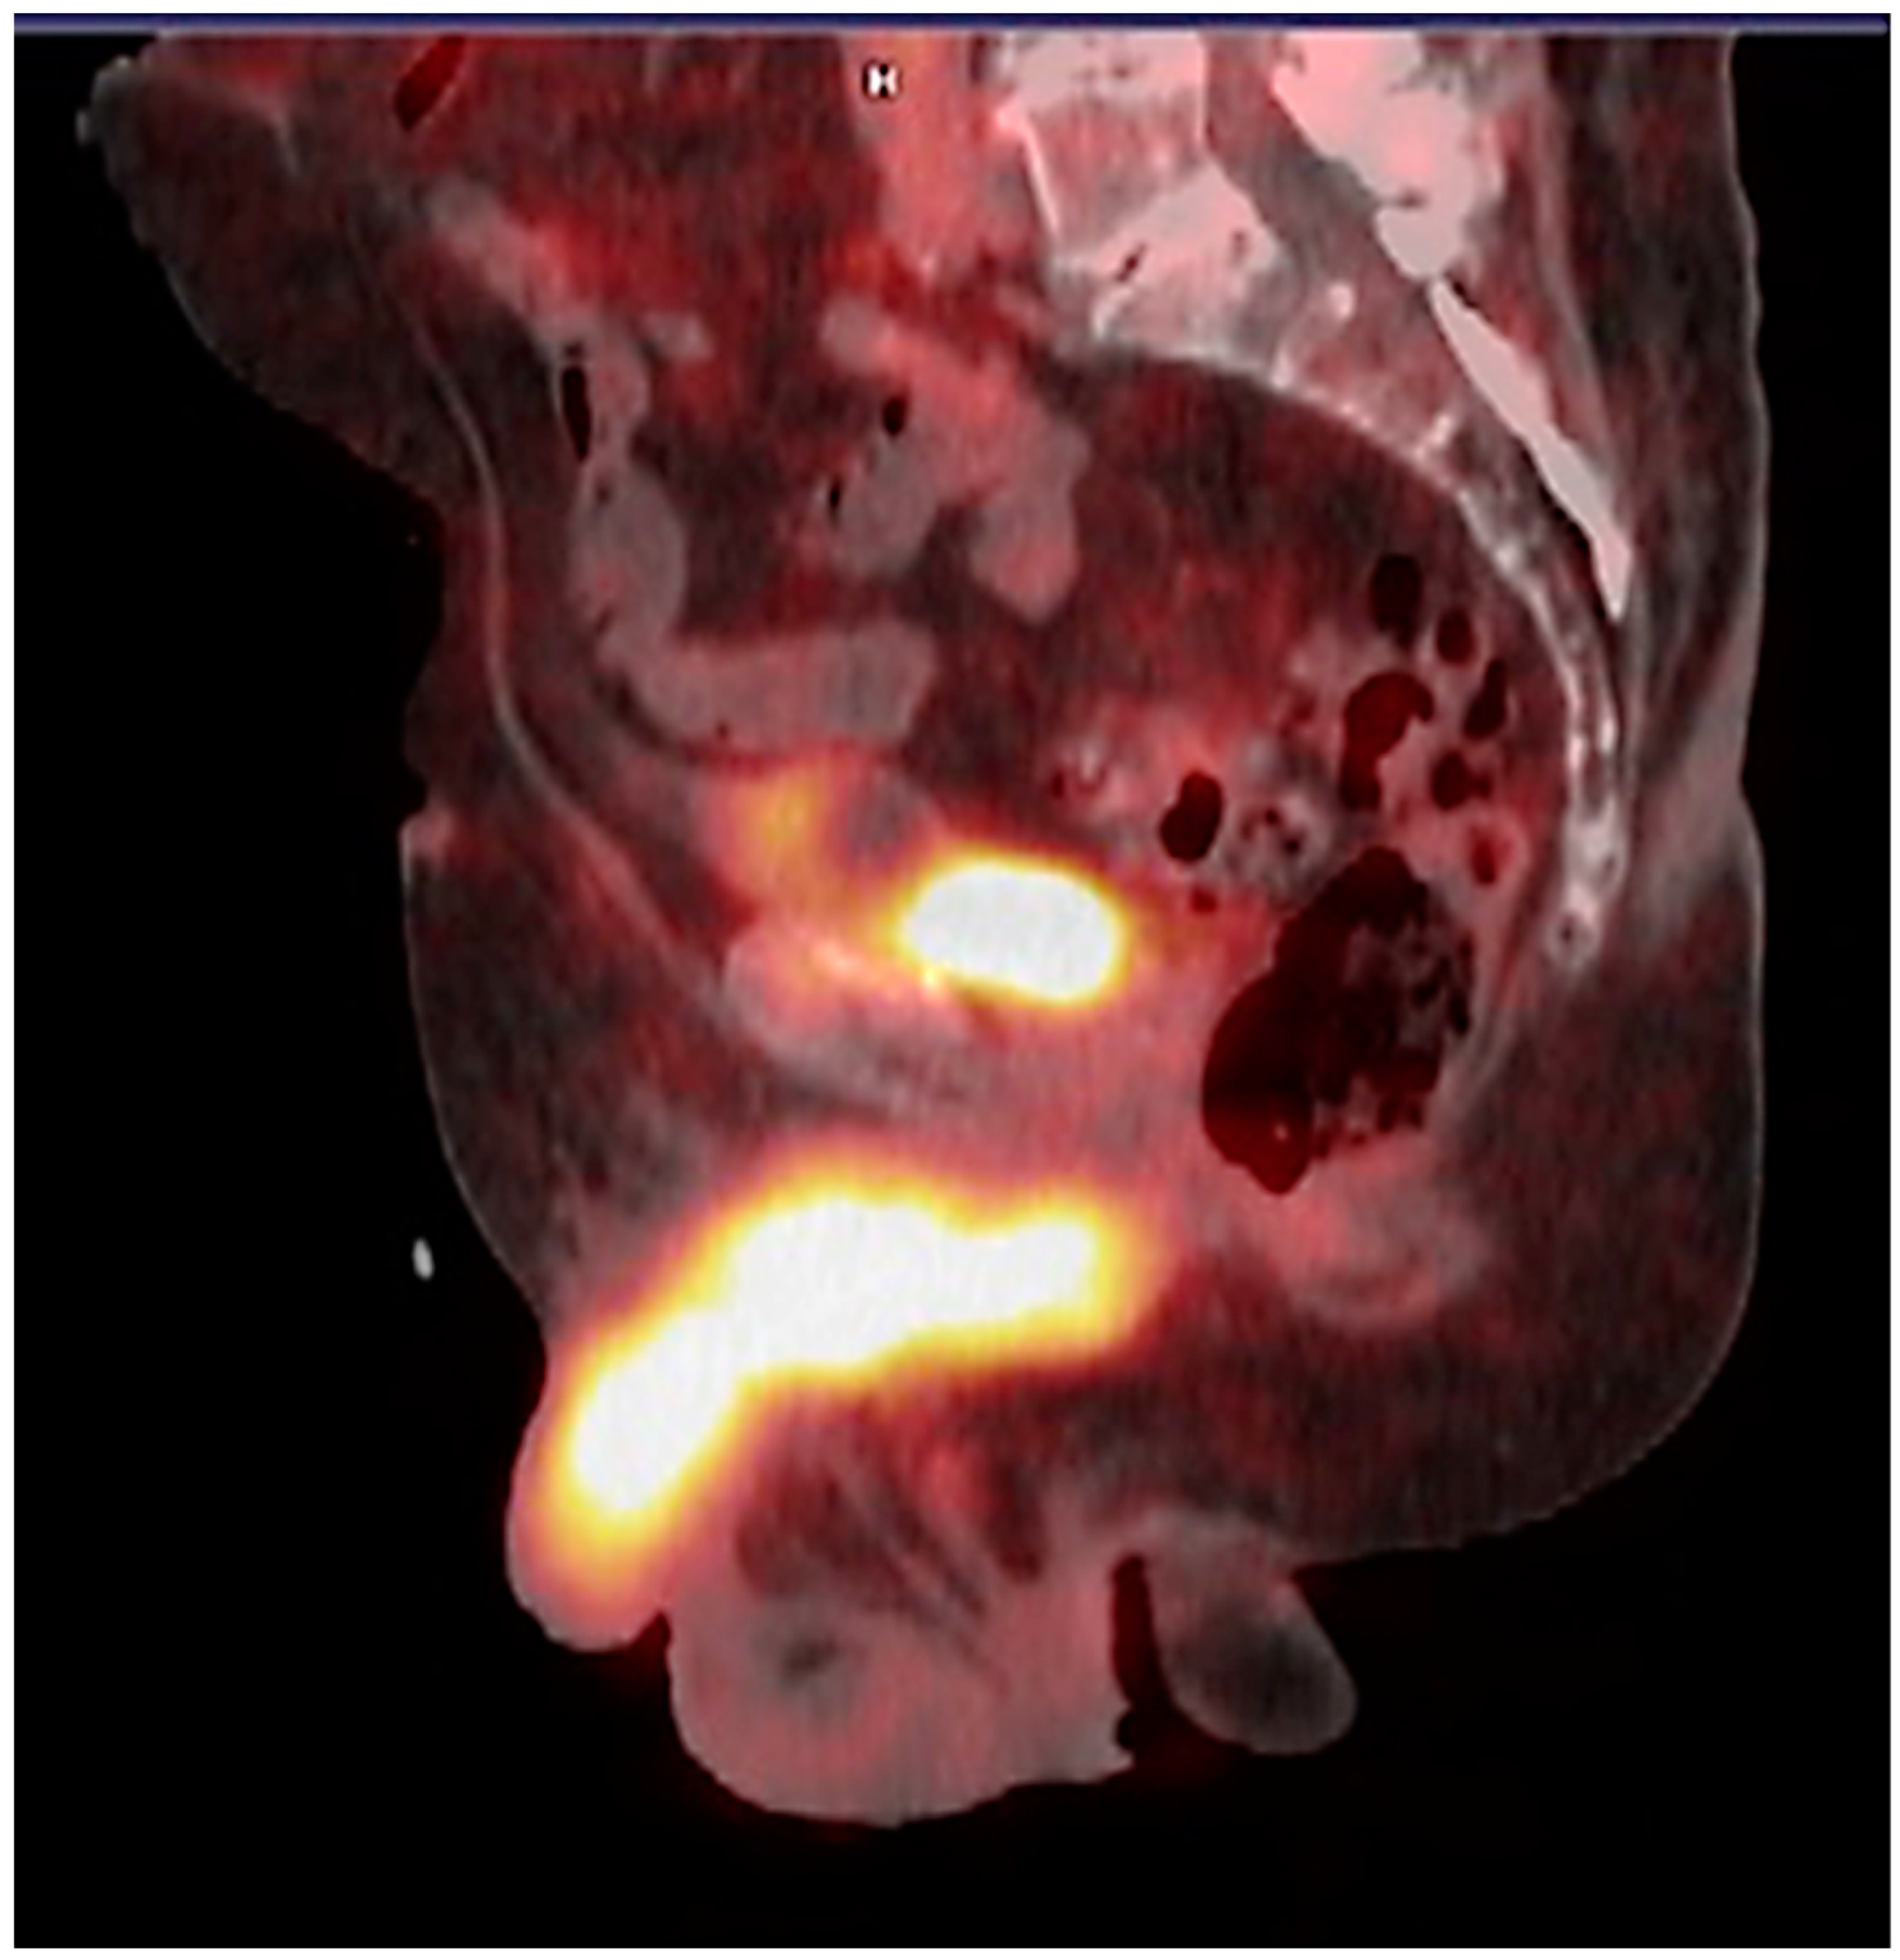

7.1. 177Lu-PSMA

7.2. 225Ac-PSMA